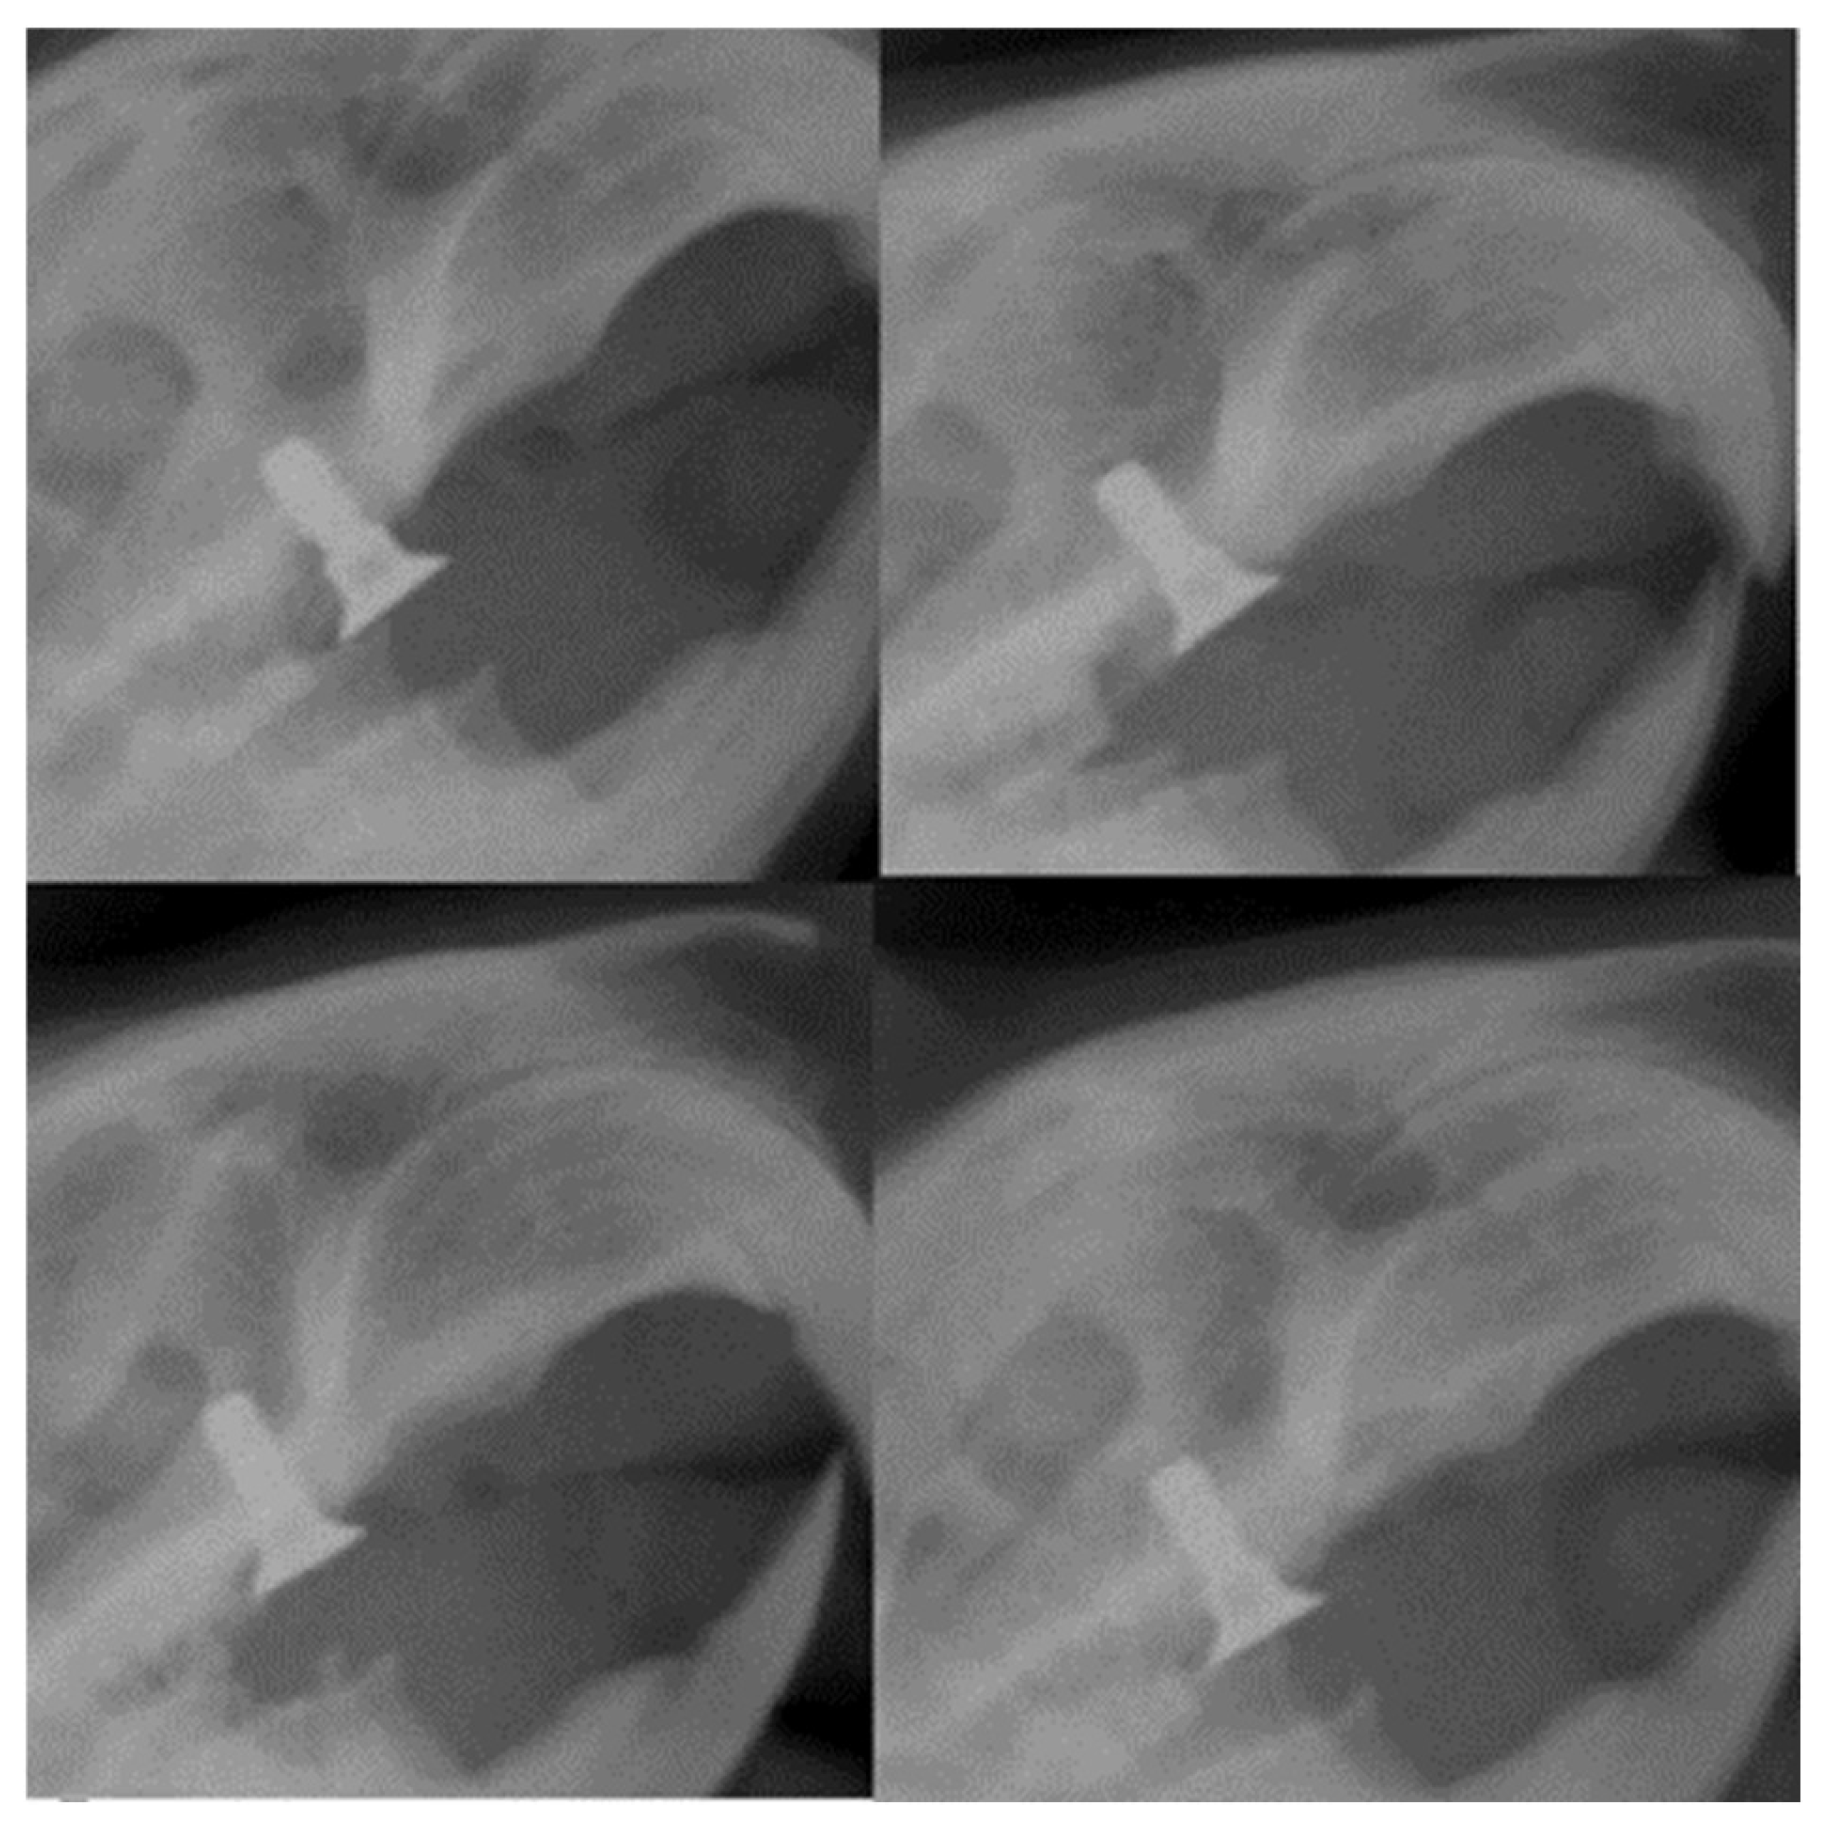

Radiological assessment is critical after implant placement, as the alveolar ridge’s height, width, and contour must be determined precisely. In the case of our study, the results showed an excellent fixation at the level of the alveolar ridge, the implant being in a parallel position with the remaining molars on the dental arch (Figure 14).

In peri-implant disease, radiographic images can assess the height of the alveolar bone in relation to the implant structure. In the case of our experiment, after the completion of the six weeks of bacterial contamination, it was possible to observe the displacement of the implants from the position parallel to the roots of the collateral teeth and a reduction in the bone density at the edge of the alveolar ridge (Figure 15).

Figure 14. Radiographic images 30 days after placement of the implants in rats showing their parallel position with the rest of the teeth and the height concerning the dental plaque.

Figure 15. Radiological appearance of the implants at the end of the period of oral contamination.